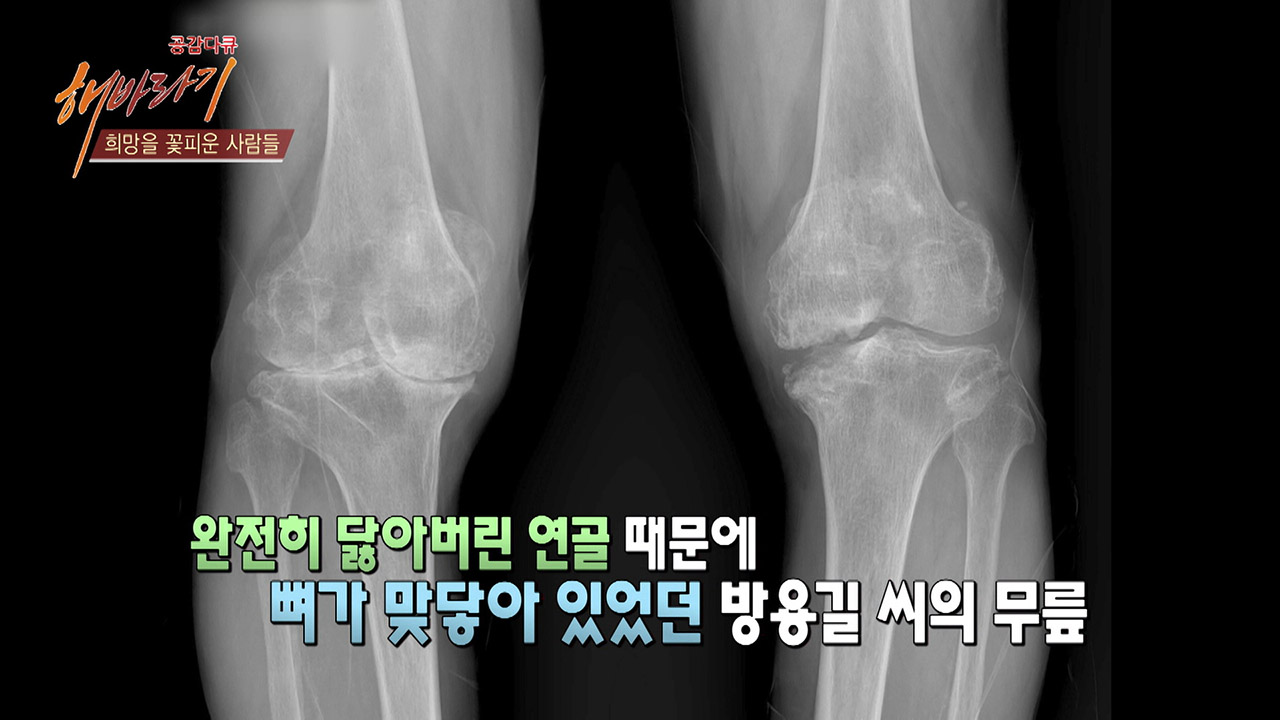

무릎관절 환자였던 방용길씨를 만나다!